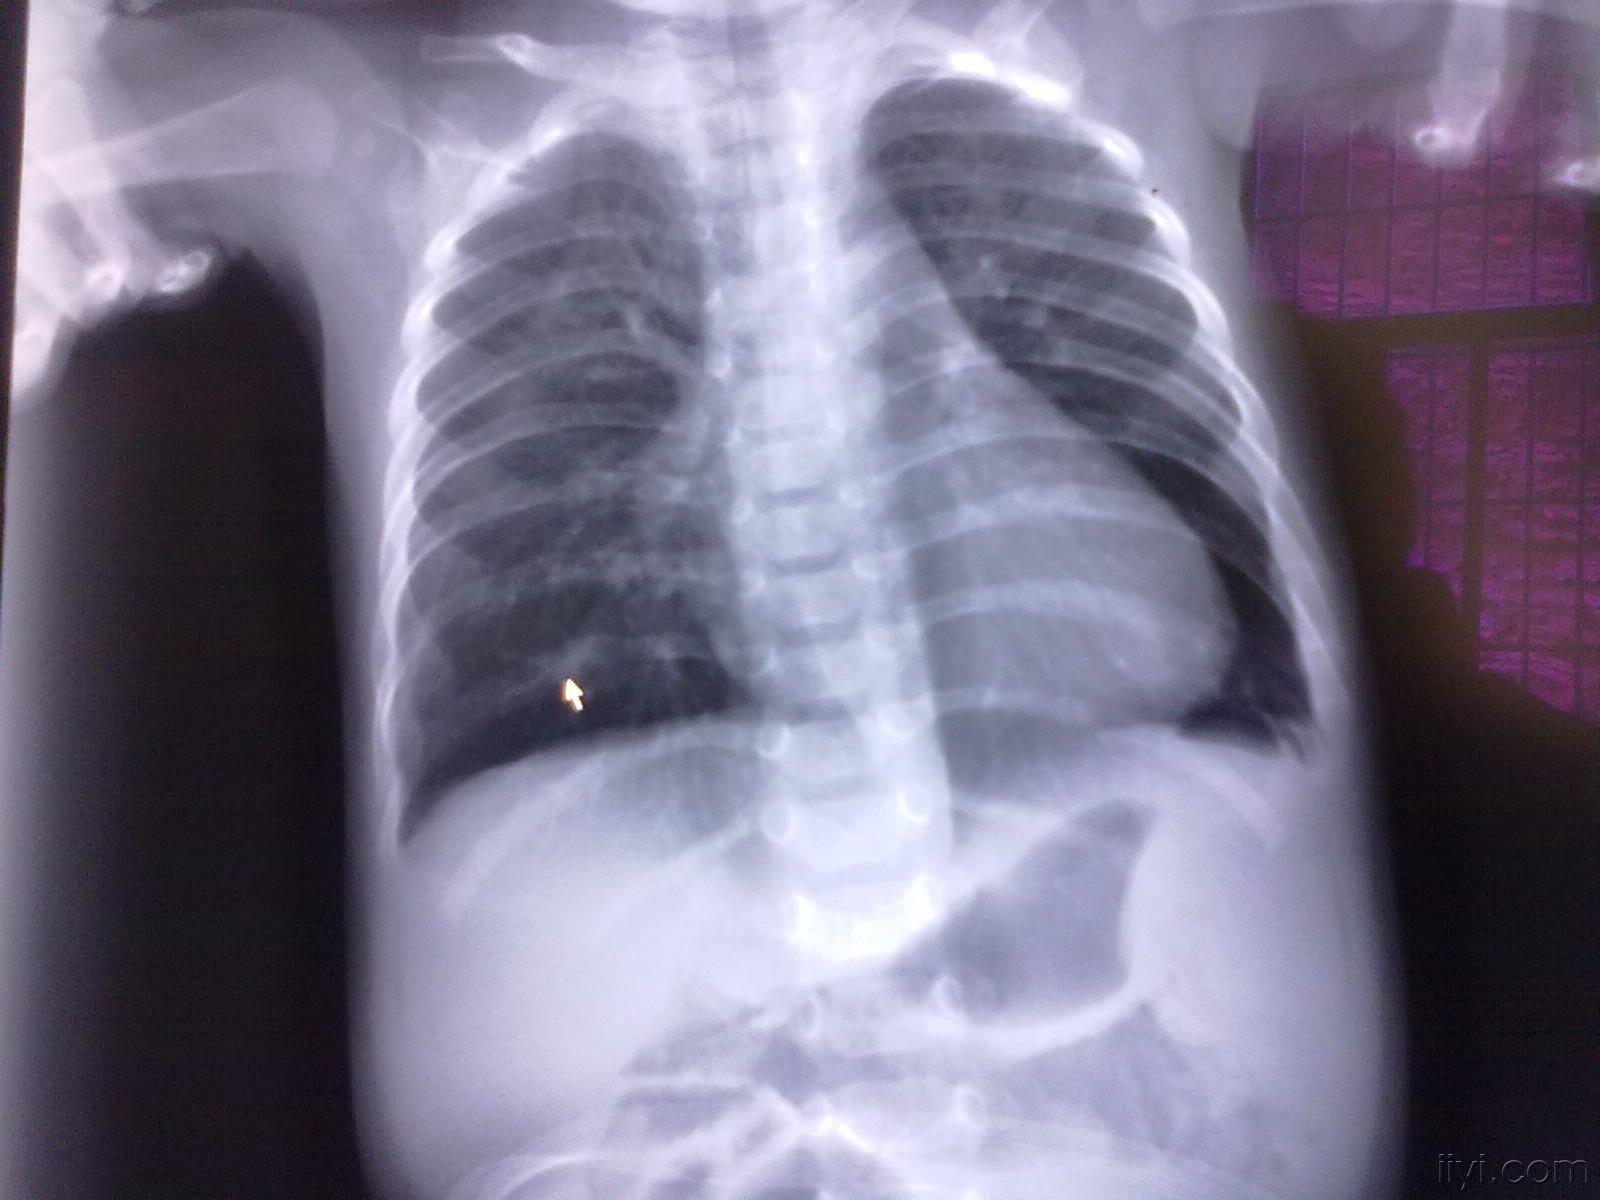

小叶性肺炎图片x片

x线显示肺段或肺叶实变,或呈小叶样浸润,可有单个或多发的液气囊腔

正确答案:支气管肺炎又称小叶性肺炎,常见病原菌为金黄色葡萄球菌

复件 右侧小叶性肺炎伴左肺气肿.jpg

支气管肺炎又称小叶性肺炎,肺炎多发生于冬春寒冷季节及气候骤变时,但